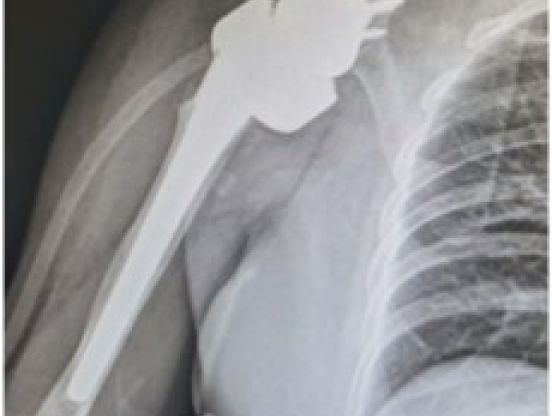

• 反肩关节置换治疗老年复杂肱骨近端骨折术后合并肩关节脱位

宁凡友

河南省洛阳正骨医院(河南省骨科医院)